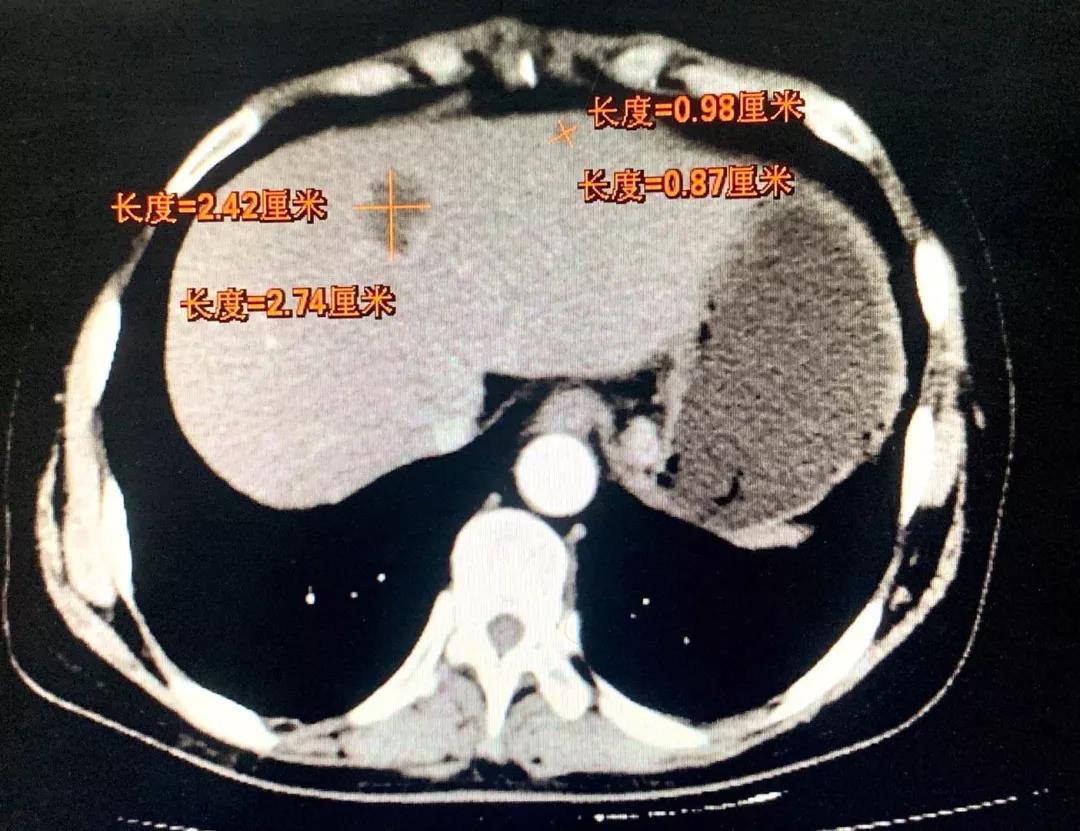

转化5周期

8月前患者就诊于晋城市某医院行胃镜示:胃癌,病理示:腺癌。进一步行腹部增强CT示:贲门胃底小弯侧占位,周围见肿大淋巴结;肝内低密度肿块影,考虑转移。遂就诊于和济医院,入院诊断为:“1.胃癌肝转移(cT4N2M1) 2.肝脏多发囊肿3.原发性高血压(2级,低危组)4.卵巢囊肿切除术后”。经医院消化病中心MDT讨论,并与患者及家属充分沟通后,决定先为其行转化治疗(方案:DOS)。转化治疗2个周期后患者症状明显好转,体重增加约10kg。肿瘤原发病灶较前缩小、肝脏转移灶较前缩小。继续行转化治疗(方案:DOS)3个周期后,患者肿瘤原发病灶较前增大、肝脏转移灶较前继续缩小。经和济医院消化病中心再次MDT讨论并与患者及家属充分沟通后,决定手术治疗。术中胃肠外科张晋杰医师、张康康医师先行腹腔镜辅助根治性全胃切除术+D2淋巴结清扫+Roux-en-Y吻合术,术中邀请肝胆外科主任程丹桂主任医师、刘军廷副主任医师以及超声室武鹏副主任医师行彩超定位下左肝转移病灶射频消融术。术中射频消融在保证对左肝转移病灶精准处理的前提下,对肝脏以最小的创伤,起到最佳的治疗效果,整个手术创伤小,术后第3日开始进流食,5日行上消化道造影提示:未见吻合口瘘。目前患者已恢复正常进食,痊愈出院。